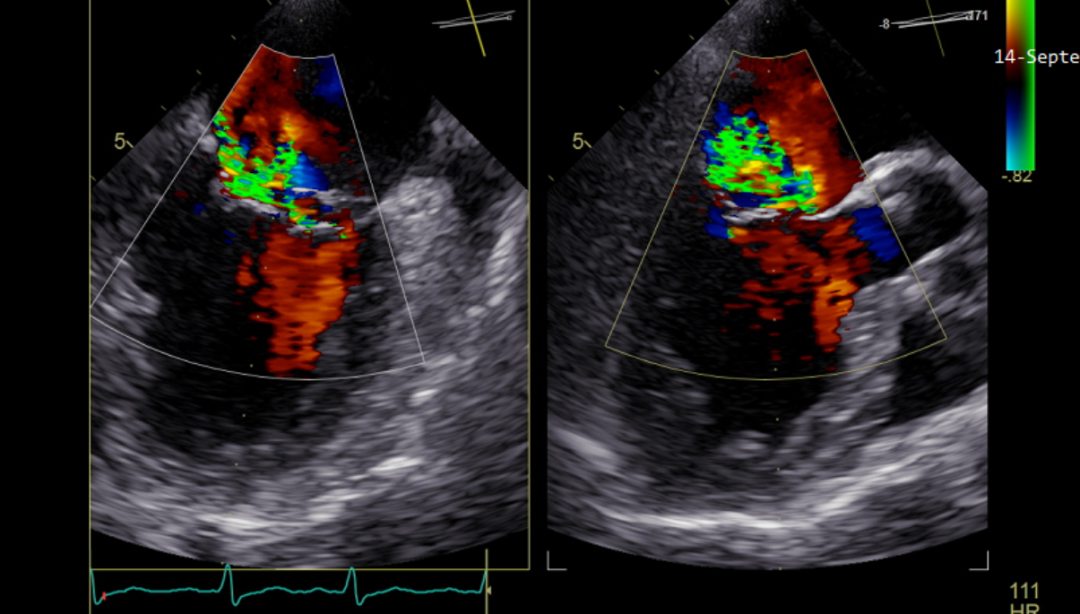

手术于全麻下进行,手术采用经股静脉穿刺房间隔途径,将导管鞘系统送入患者左心房,到达二尖瓣口,全程在TEE引导下,术者通过评估二尖瓣反流位置、瓣叶脱垂位置以及反流程度等,精准夹合二尖瓣叶,患者一准确植入一枚二尖瓣夹,瓣膜夹位置稳定,植入后反流基本消失(图3),耗时两个半小时,二尖瓣跨瓣平均压力阶差1mmHg,左心房平均压力即刻从28mmHg降到10mmHg,患者二较患者一难度稍大,但在术者娴熟的操作中手术更加顺畅,依然一枚二尖瓣钳夹完成,二尖瓣跨瓣平均压力阶差1mmHg,左心房平均压力即刻从27mmHg降到7mmHg,瓣膜夹位置稳定,植入后反流基本消失(图4),耗时两小时,两位患者术后均恢复良好,三、四天后遂出院。

图3 患者一,反流基本消失

图4 患者二,反流完全消失